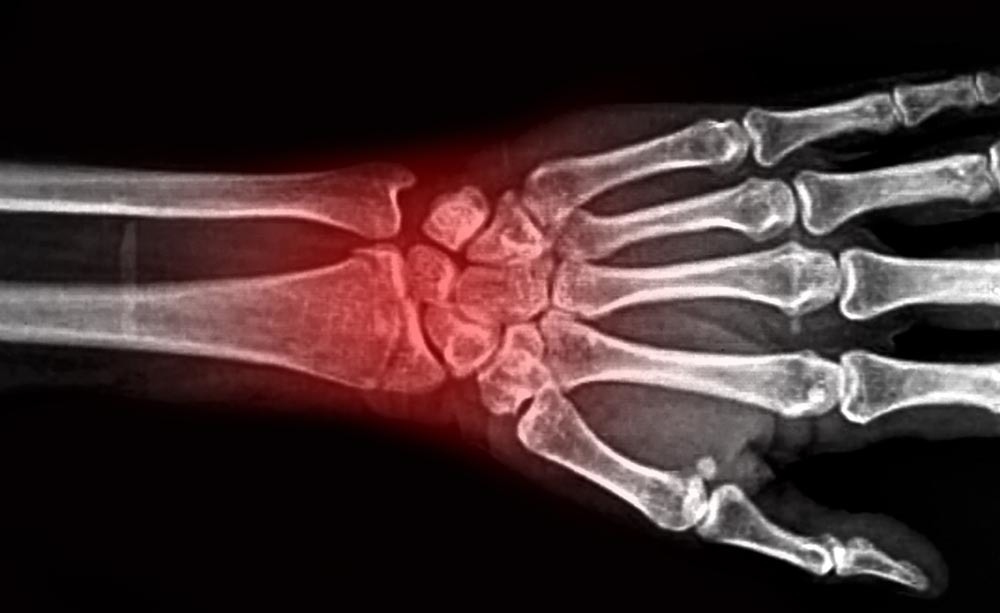

Il recupero delle funzionalità del polso, dopo la frattura del radio

Rottura del polso e fisioterapia

Le fratture distali che interessano la zona del radio, noto come polso, possono essere di tipi diversi e diversi sono anche i modi in cui le persone rispondono alle svariate terapie. Ecco perché è complesso prevedere lo sviluppo del processo di guarigione.